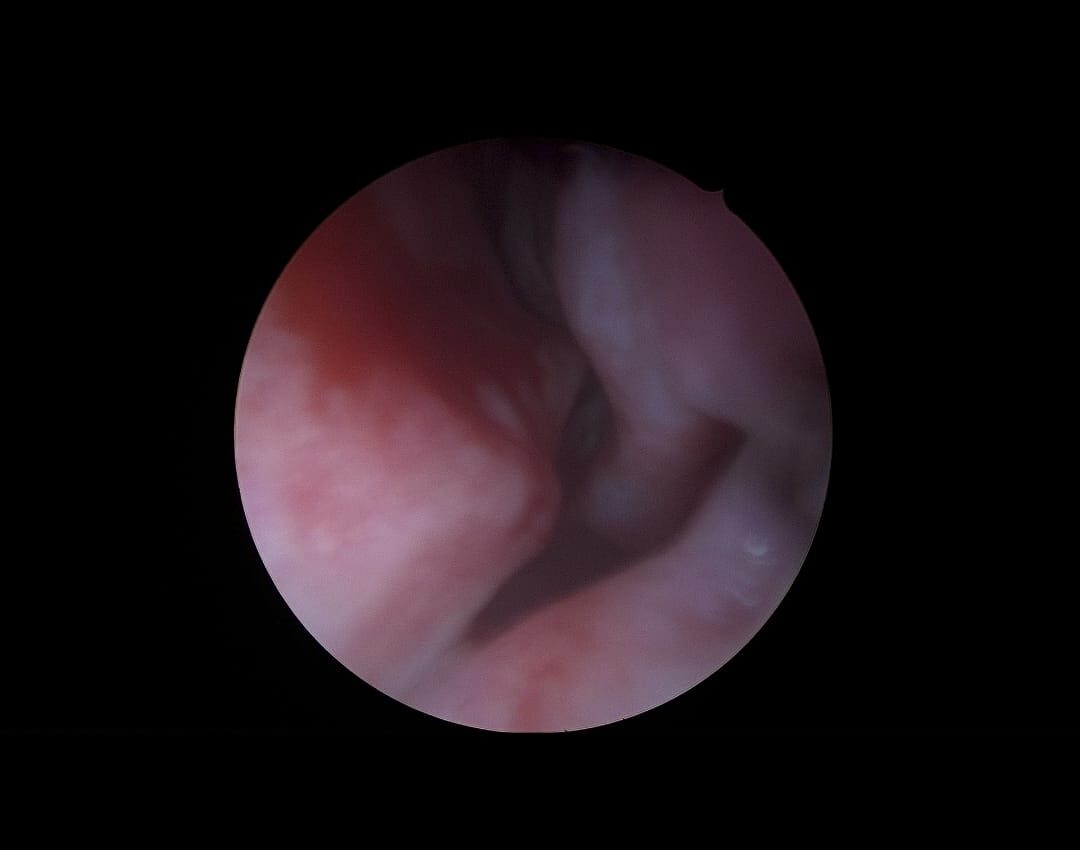

• تشخيص أمراض الأنف بالمنظار

• تقويم الحاجز الأنفي والغضاريف

• استئصال لحميات الأنف والجيوب الأنفية

• فحص النحجرة بالمنظار الحنجري